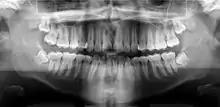

A dental panoramic radiograph, showing the maxilla and mandible, all the teeth including the "wisdom teeth," the frontal and maxillary sinuses, the nasal cavity and the temporomandibular joint and other near by head and neck anatomy.

A panoramic radiograph is a panoramic scanning dental X-ray of the upper and lower jaw. It shows a two-dimensional view of a half-circle from ear to ear. Panoramic radiography is a form of focal plane tomography; thus, images of multiple planes are taken to make up the composite panoramic image, where the maxilla and mandible are in the focal trough and the structures that are superficial and deep to the trough are blurred.